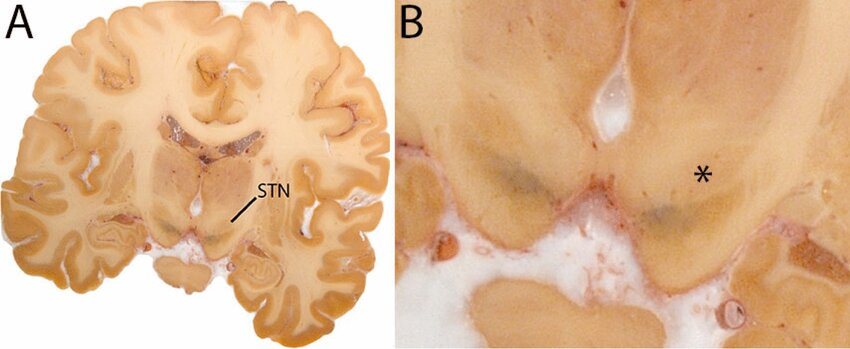

Subthalamatic nucleus